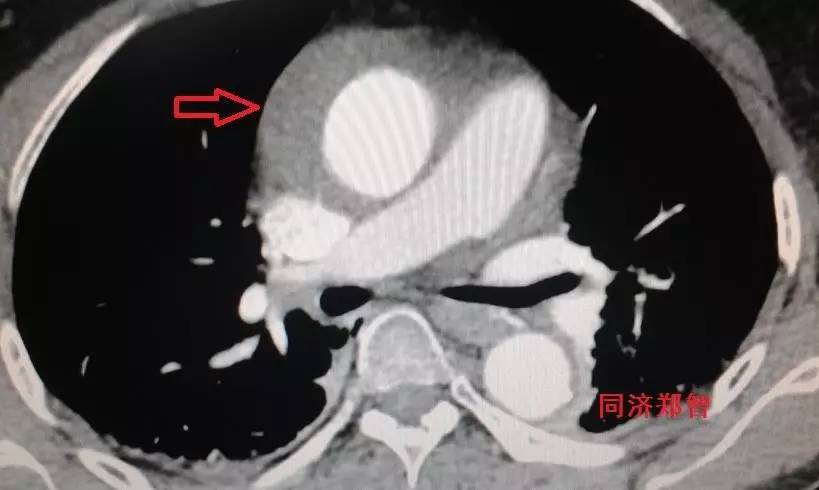

CT增强后证实为升主动脉壁间血肿(图4),如红箭头所示。

图4